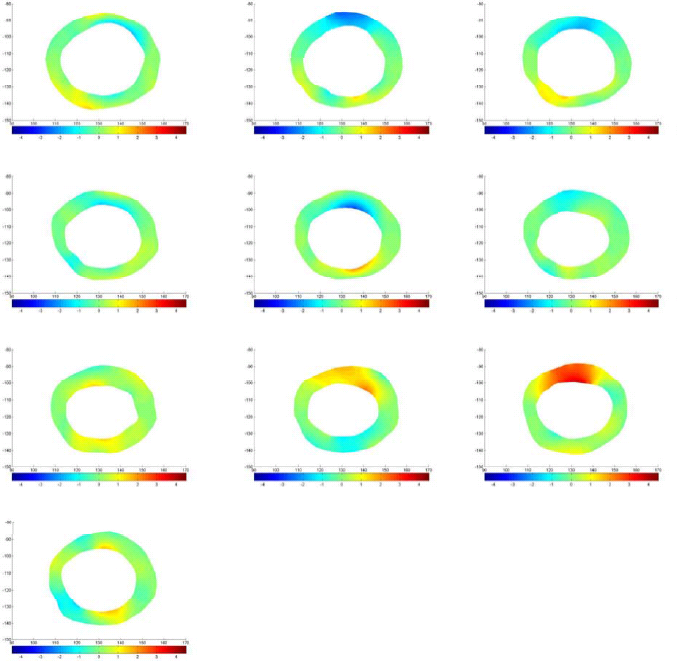

Using the displacement vectors, the boundary conditions of the FEM model can be defined. After applying the boundary conditions and then meshing the domain with a fine triangular mesh, FEM is used to solve the governing equation of deformation. The result of FEM is the displacement values in and directions in the deforming body’s domain. Fig.9 shows the results of FEM for two slices of subjects 25 and 23 during systole for horizontal and vertical displacements.

which in 2D case can be simplified because . Using this parameter we are able to monitor the changes in strain maps of heart muscle during deformation. Computing effective strain values for different slices of cardiac muscle, these values are used for comparison between healthy and MI subjects. Fig. 10 represent the results for first slice of healthy subjects, 18 and 25, and MI subject 23 during the cardiac cycle.